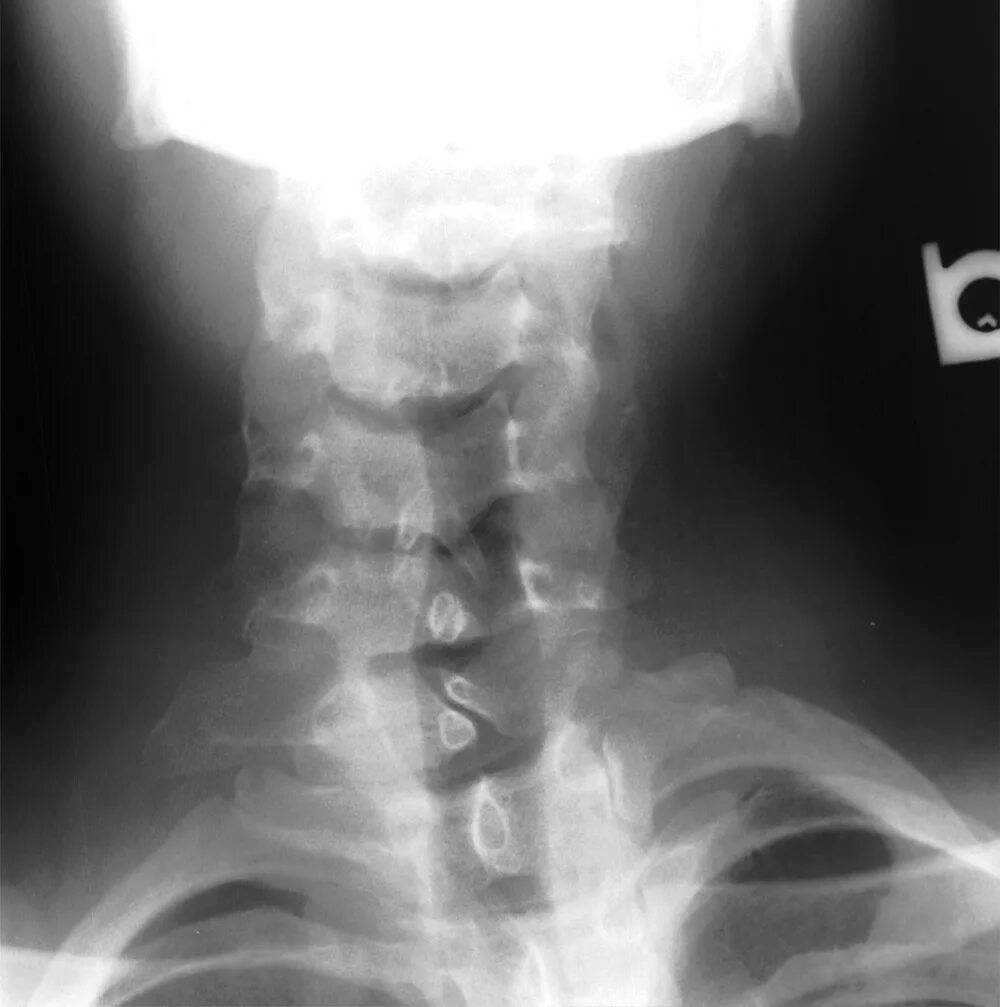

Незаращение дужки позвонка